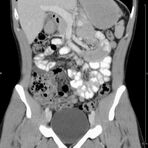

Abdomen (Bauch und Becken)

• Diagnostik von entzündlichen und tumorösen Erkrankungen der Bauchorgane

• Diagnostik von akuten Notfällen wie Darmverschluss, Hohlorganperforation oder Traumafolgen

• Darstellung der großen Gefäße zur Erkennung von Gefäßverschlüssen (z. B. Mesenterial - Arterienembolie oder Einengungen von Gefäßen (z. B. Nierenarterien)

• Darstellung und Therapieplanung von Aneurysmen (CT- Angiographie)

• Virtuelle Kolonographie zur Darstellung des Dickdarmes z. B. bei Kontraindikation zur Darm-Spiegelung oder nur unvollständig durchführbarer Koloskopie.

Sollte es z. B. bei einer Untersuchung des Bauchraumes erforderlich sein, Kontrastmittel in der Vorbereitungsphase zu trinken, so dauert dies ca. 45 Minuten, damit sich das Kontrastmittel gleichmäßig im Dünndarm und Dickdarm verteilen kann.

In manchen Fällen – vor allem bei der Untersuchung von Hals, Thorax und Abdomen – reicht das Darstellungsvermögen des Gerätes allein nicht aus, deshalb werden kontraststeigernde Mittel, sog. Kontrastmittel, in das Blut (zum Darstellen oder Abgrenzen von Gefäßen oder auch zur Unterscheidung von gesundem und krankem Gewebe) oder auch zum Trinken (zur besseren Abgrenzung des Magen-Darm-Traktes) verabreicht.

• Orale (Trink-) Kontrastmittel:

Kontrastmittel, die getrunken werden, sollen helfen, den Darm gegen andere Organe, z. B. gegen Lymphknoten besser abzugrenzen. Es handelt sich dabei um jod- oder bariumhaltige Lösungen. Je nach Fragestellung sollen Sie vor der Untersuchung davon 0,5- 2 Liter trinken. Da der Darm sehr lang ist, dauert es ca. 40 Minuten bis 1 Stunde, bis die Darmschlingen vollständig kontrastiert sind. Es ist wichtig, das KM möglichst langsam und gleichmäßig zu trinken, damit sich alle Darmabschnitte gleichmäßig kontrastieren. Unser Personal wird Ihnen dies vor der Untersuchung genau erklären.